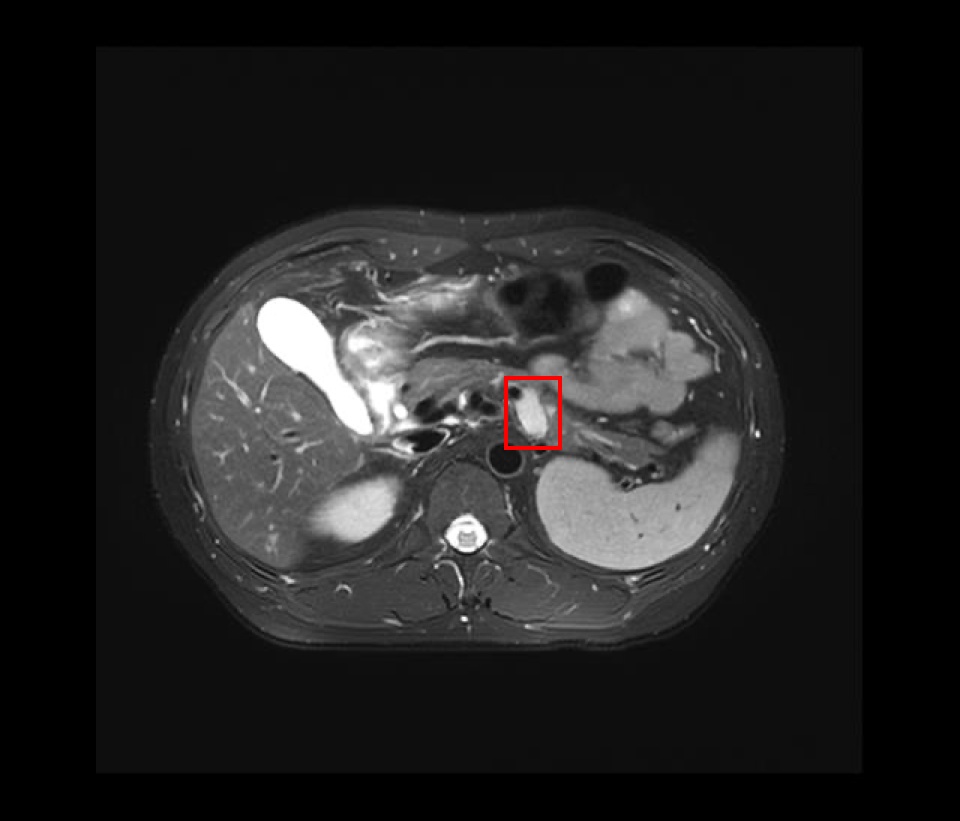

治疗前、疫苗前/后 影像图